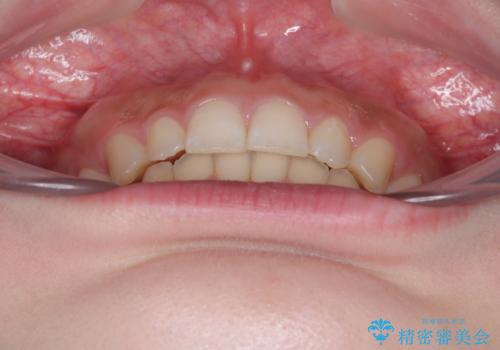

ディープバイトを短期間で改善 ワイヤー矯正治療

左上の歯列は補助装置により速やかに移動し、1年程度で奥歯の咬み合わせが改善され、1年3ヶ月の短期間でしっかりと仕上げることができました。